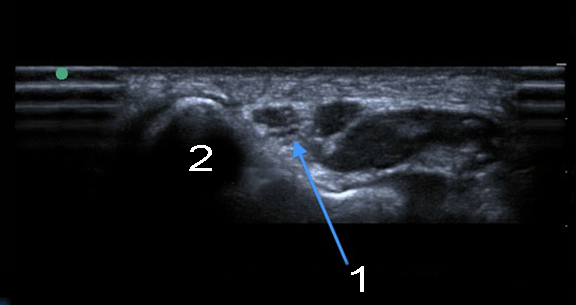

肘部管短軸の画像

肘尺骨神経肘部管横

内側上顆